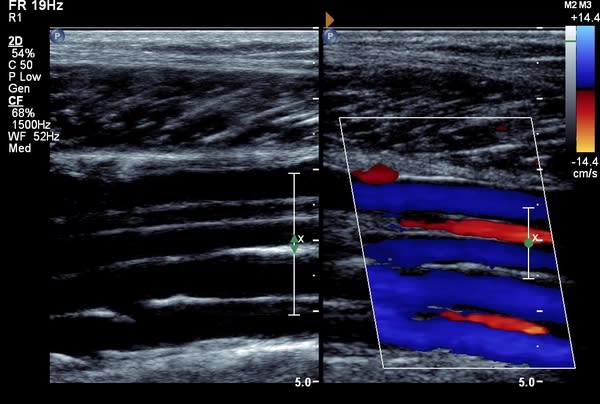

Numi Scan offer a same day service to diagnose leg DVT for £120